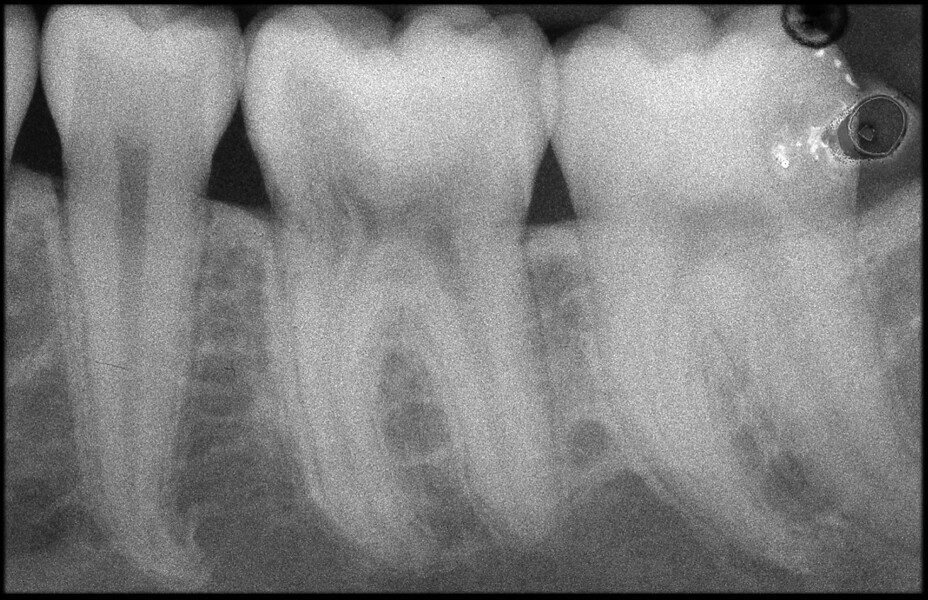

Use of 3D technology in the diagnosis and treatment of endodontic disease